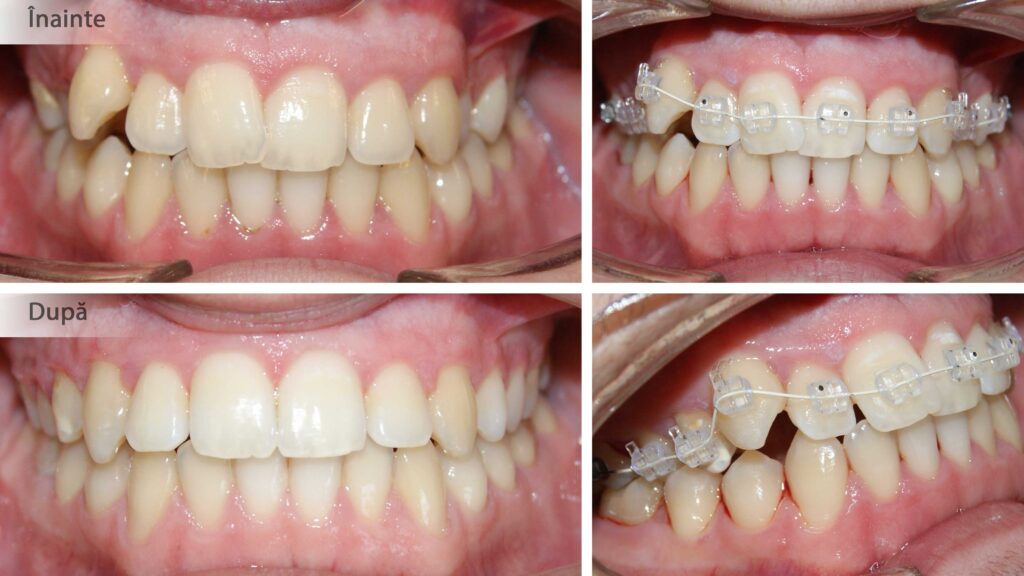

Corectarea ortodontică a angrenajului invers, un zâmbet de mult visat!